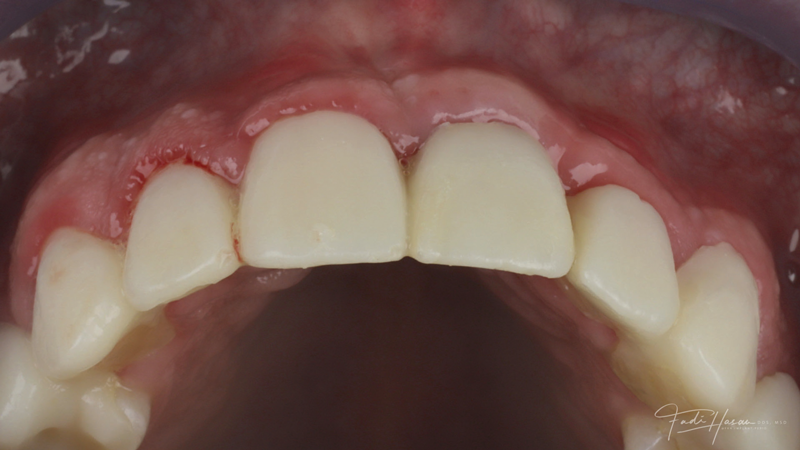

(2.) Preoperative retracted maxillary view of an implant-supported restoration at the site of tooth No. 9 demonstrating a peri-implant soft-tissue dehiscence extending approximately 3-mm apical to the gingival margin of tooth No. 8. Note the thin and erythematous marginal tissue evident at the zenith.

Figure 2

The patient in this case had undergone implant therapy at the site of tooth No. 9 and was restored with a cement-retained restoration more than 5 years prior. At presentation, the site demonstrated a peri-implant soft-tissue dehiscence that extended approximately 3-mm apical to the gingival margin of tooth No. 8. Thin and erythematous marginal tissue was evident at the zenith (Figure 2). The crown was removed, and a partial thickness flap was reflected using a papilla-sparing incision design. This revealed that the implant was positioned too far facially and that its body was visible through a very thin layer of bone (Figure 3 and Figure 4). The first objective of treatment was to minimize the facial extent of the emerging abutment and crown. To accomplish this, the facially positioned abutment and implant crown margin were both recontoured. The second treatment objective was to provide additional supracrestal soft tissue that would more adequately maintain the peri-implant margin. The tuberosity was selected as a donor site due to its dense, high-quality connective tissue, low propensity for shrinkage, and association with minimal patient discomfort. Once the graft was secured (Figure 5 through Figure 7), the flap was coronally positioned (Figure 8). After a healing period of 2 weeks, the margin of tooth No. 9 exhibited an ideal position in relation to its contralateral counterpart and demonstrated increased soft tissue thickness (Figure 9). Three months postoperatively, further healing had improved the esthetics and the position of the margin had been maintained (Figure 10).